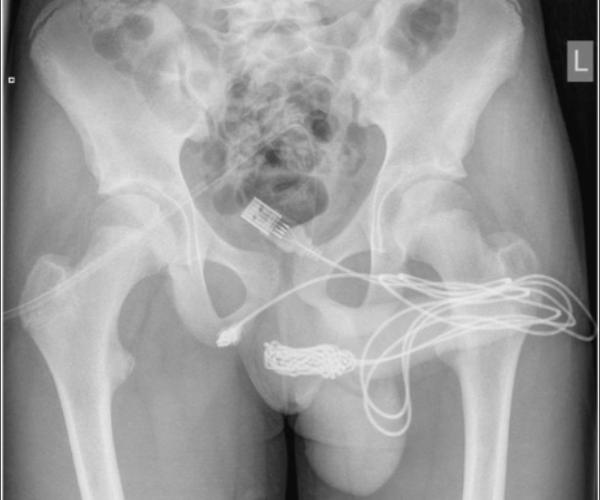

ஆணுறுப்பின் நீளத்தை அளக்க யூஎஸ்பி கேபிளை பிறப்புறுப்பில் நுழைத்த சிறுவன்.. கடைசியில் நடந்தது என்ன?

லண்டன்: லண்டனில் ஆணுறுப்பு எத்தனை நீளமாக இருக்கிறது என்பதை தெரிந்து கொள்ள தனது பிறப்புறுப்பில் யூஎஸ்பி கேபிளை நுழைத்த போது அது சிக்கிக் கொண்ட சம்பவம் அதிர்ச்சியை ஏற்படுத்தியுள்ளது.

ஆனால் கேபிள் வரவில்லை, எங்கோயோ சிக்கிக் கொண்டது. இழுத்து இழுத்து பார்த்து முடியவில்லை. அந்த கேபிளில் நிறைய முடிச்சுகள் இருந்ததால் அவன் சிறுநீர் கழித்த போது ரத்தம் கசிந்தது. இதையடுத்து தாயிடம் ரத்தம் வருவதை சொல்லியதை அடுத்து சிறுவனை மருத்துவமனைக்கு அழைத்து சென்றார்.

அப்போது உலோக கம்பியை கொண்டு கேபிளை அகற்ற மருத்துவர்கள் முயற்சிததனர். ஆனால் அது கடினமான வேலையாக இருந்தது. இதனால் அறுவை சிகிச்சை செய்ய வேண்டிய நிலை ஏற்பட்டது. அறுவை சிகிச்சை மூலமே அந்த கேபிள் வெளியே எடுக்கப்பட்டது.

அப்போதுதான் அந்த கேபிள் சிறுவனின் ஆண் குறிக்குள் 70 செ.மீ. அளவு உள்ளே இருந்தது. இதையடுத்து மருத்துவர்களின் கண்காணிப்பில் 24 மணி நேரம் வைக்கப்பட்டிருந்த சிறுவன் டிஸ்சார்ஜ் செய்யப்பட்டான். விளையாட்டு வினையாகும் என்பதற்கு இது சிறந்த உதாரணம்.